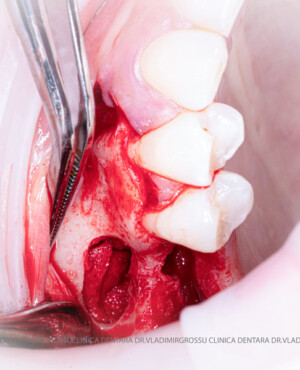

Aditia gingivală este o procedură chirurgicală ce corectează diverse probleme estetice și funcționale, cum ar fi recesiunea gingivală. În implantologia modernă, aditia de țesut moale este utilizată aproape în fiecare intervenție de inserție a implantului dentar pentru a asigura un aspect estetic natural și o bună integrare a implantului în cavitatea bucală.

Adiția osoasă are un rol crucial pentru poziționarea corectă și stabilă a implanturilor dentare. Clinica stomatologică Dr. Grossu din Chișinău promovează o abordare chirurgicală estetică și predictibilă, adaptată fiecărui caz în parte.